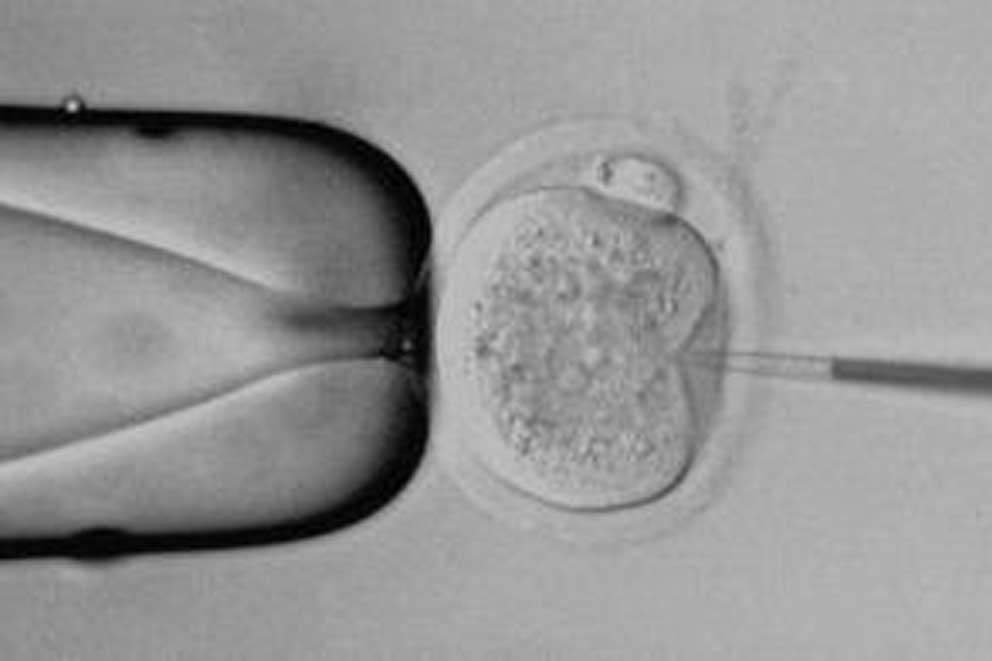

Laboratory animals

People often disagree on whether animal experiments are necessary, useful or justified, and to what extent non-animal alternatives are available. We believe that every area of animal use should be judged individually and that replacing the use of animals with humane alternatives must be the main goal.